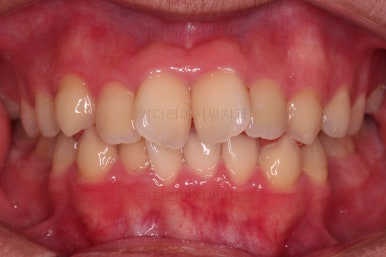

총 19개월만에 치료를 종료했습니다.

가지런한 느낌, 교합, 중앙선 등 매우 양호한 치료결과였습니다.

전후 비교입니다.

입은 약간만 들어가게끔 했고요.

웃을 때의 입매가 참 좋아졌네요.

얼굴모습에서 드러나는 치열의 느낌이 매우 좋아졌어요.